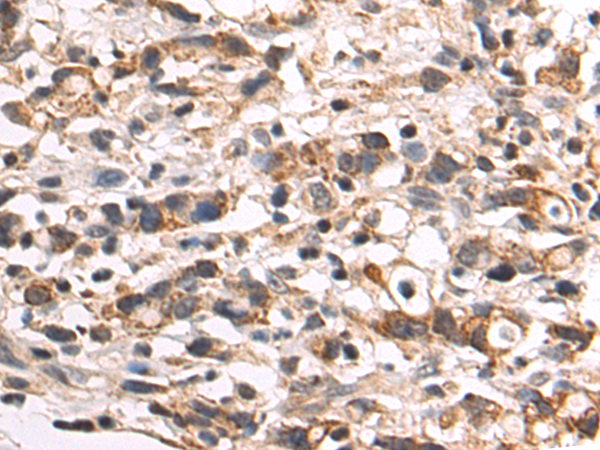

分类: 科研抗体货号: P07709别名: BMR2; PPH1; BMPR3; BRK-3; T-ALK; BMPR-II应用: IHC反应种属: Human, Mouse